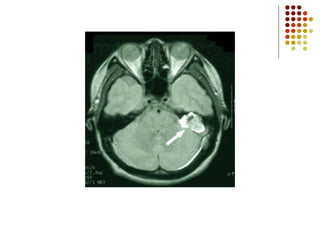

Ejemplos de Tumores

Cerebral